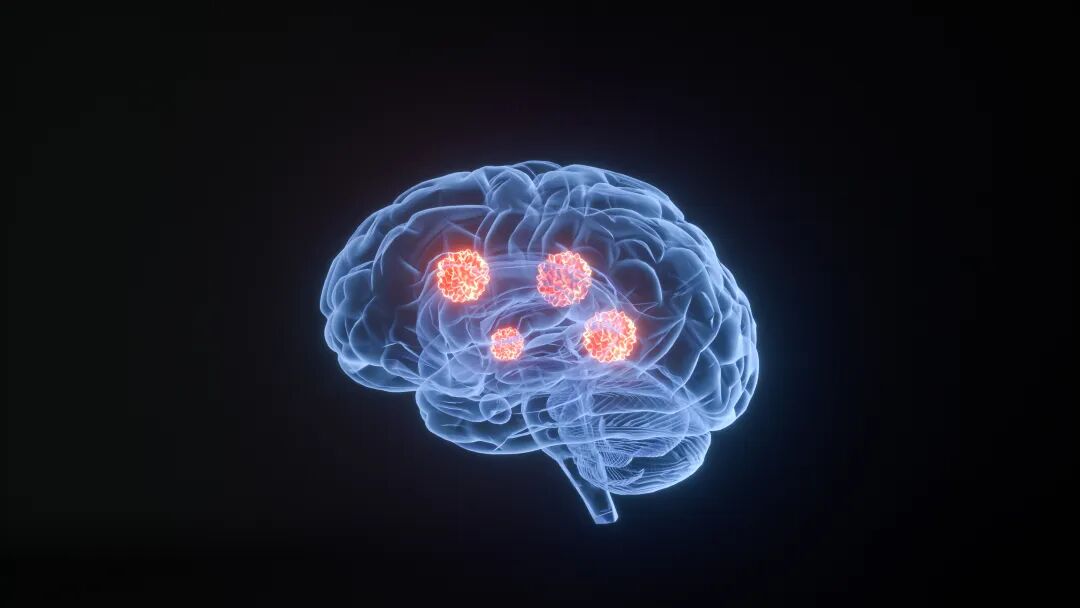

4. 脑部

脑部有血脑屏障,但癌细胞仍可突破转移,多见于肺癌、乳腺癌、黑色素瘤患者。转移后会出现头痛、头晕、视力模糊、肢体偏瘫,压迫神经中枢,危害极大,中医认为是“邪毒上扰、元神受损”。

图片